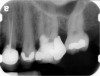

Fig 9 Preoperative radiographs showing mesial perforation.

Figure 9

Fig 10. Preoperative radiographs showing mesial perforation.

Figure 10

Clinical procedure: Once a perforation occurs, the extent of the perforation must be assessed. If there is an adjacent bony defect, the bony defect should first be filled with an osteoconductive or osteoinductive material. This can be done with a bone graft, calcium sulfate, or collagen/gelatin sponge. The dentinal portion of the tooth that has been perforated is then restored with MTA (Figure 9 through Figure 14).